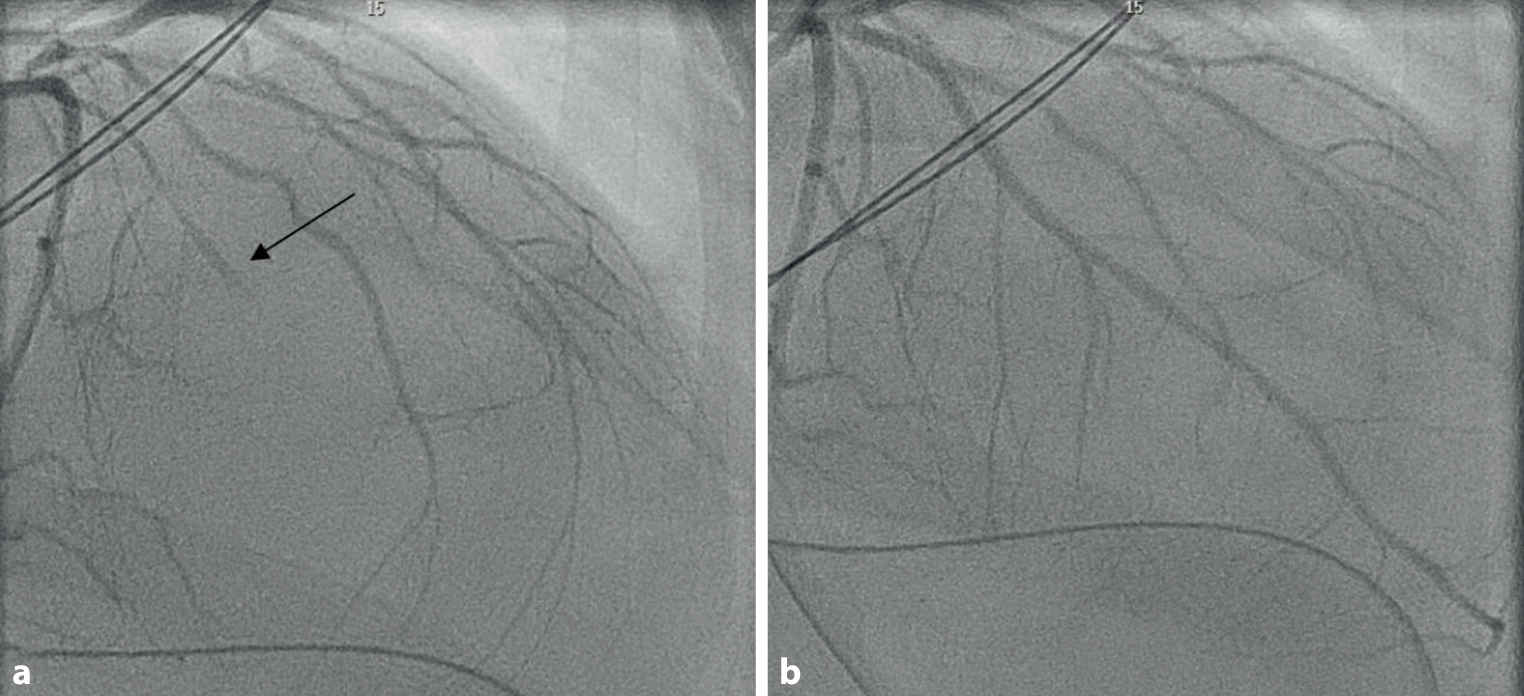

A 32-year-old pregnant woman was admitted with placental abruption, and a caesarean section was performed. Postpartum haemorrhage ensued, which was treated with oxytocin, methylergometrine and sulprostone. Shortly thereafter she developed ventricular fibrillation and cardiogenic shock. Electrocardiography showed sinus tachycardia with alternating right and left bundle branch block. Transthoracic echocardiography demonstrated a severely impaired left ventricular function with apical and septal akinesia and basal hyperkinesias. Coronary angiography revealed spasm of the left anterior descending coronary artery, which was successfully treated with intracoronary nitroglycerin (Figs. 1a, b). Because of continuing cardiogenic shock, a microaxial flow device was implanted and systemic vasodilators were started. Cardiac contractility recovered rapidly and she was discharged in good clinical condition.

a Occlusion of mid-left anterior descending artery (left anterior oblique view 1°, cranial view 30°) before and after intracoronary nitroglycerin. b Left anterior descending artery wrapping around the apex (TIMI III flow). (Right anterior oblique view 2°, cranial view 31°)